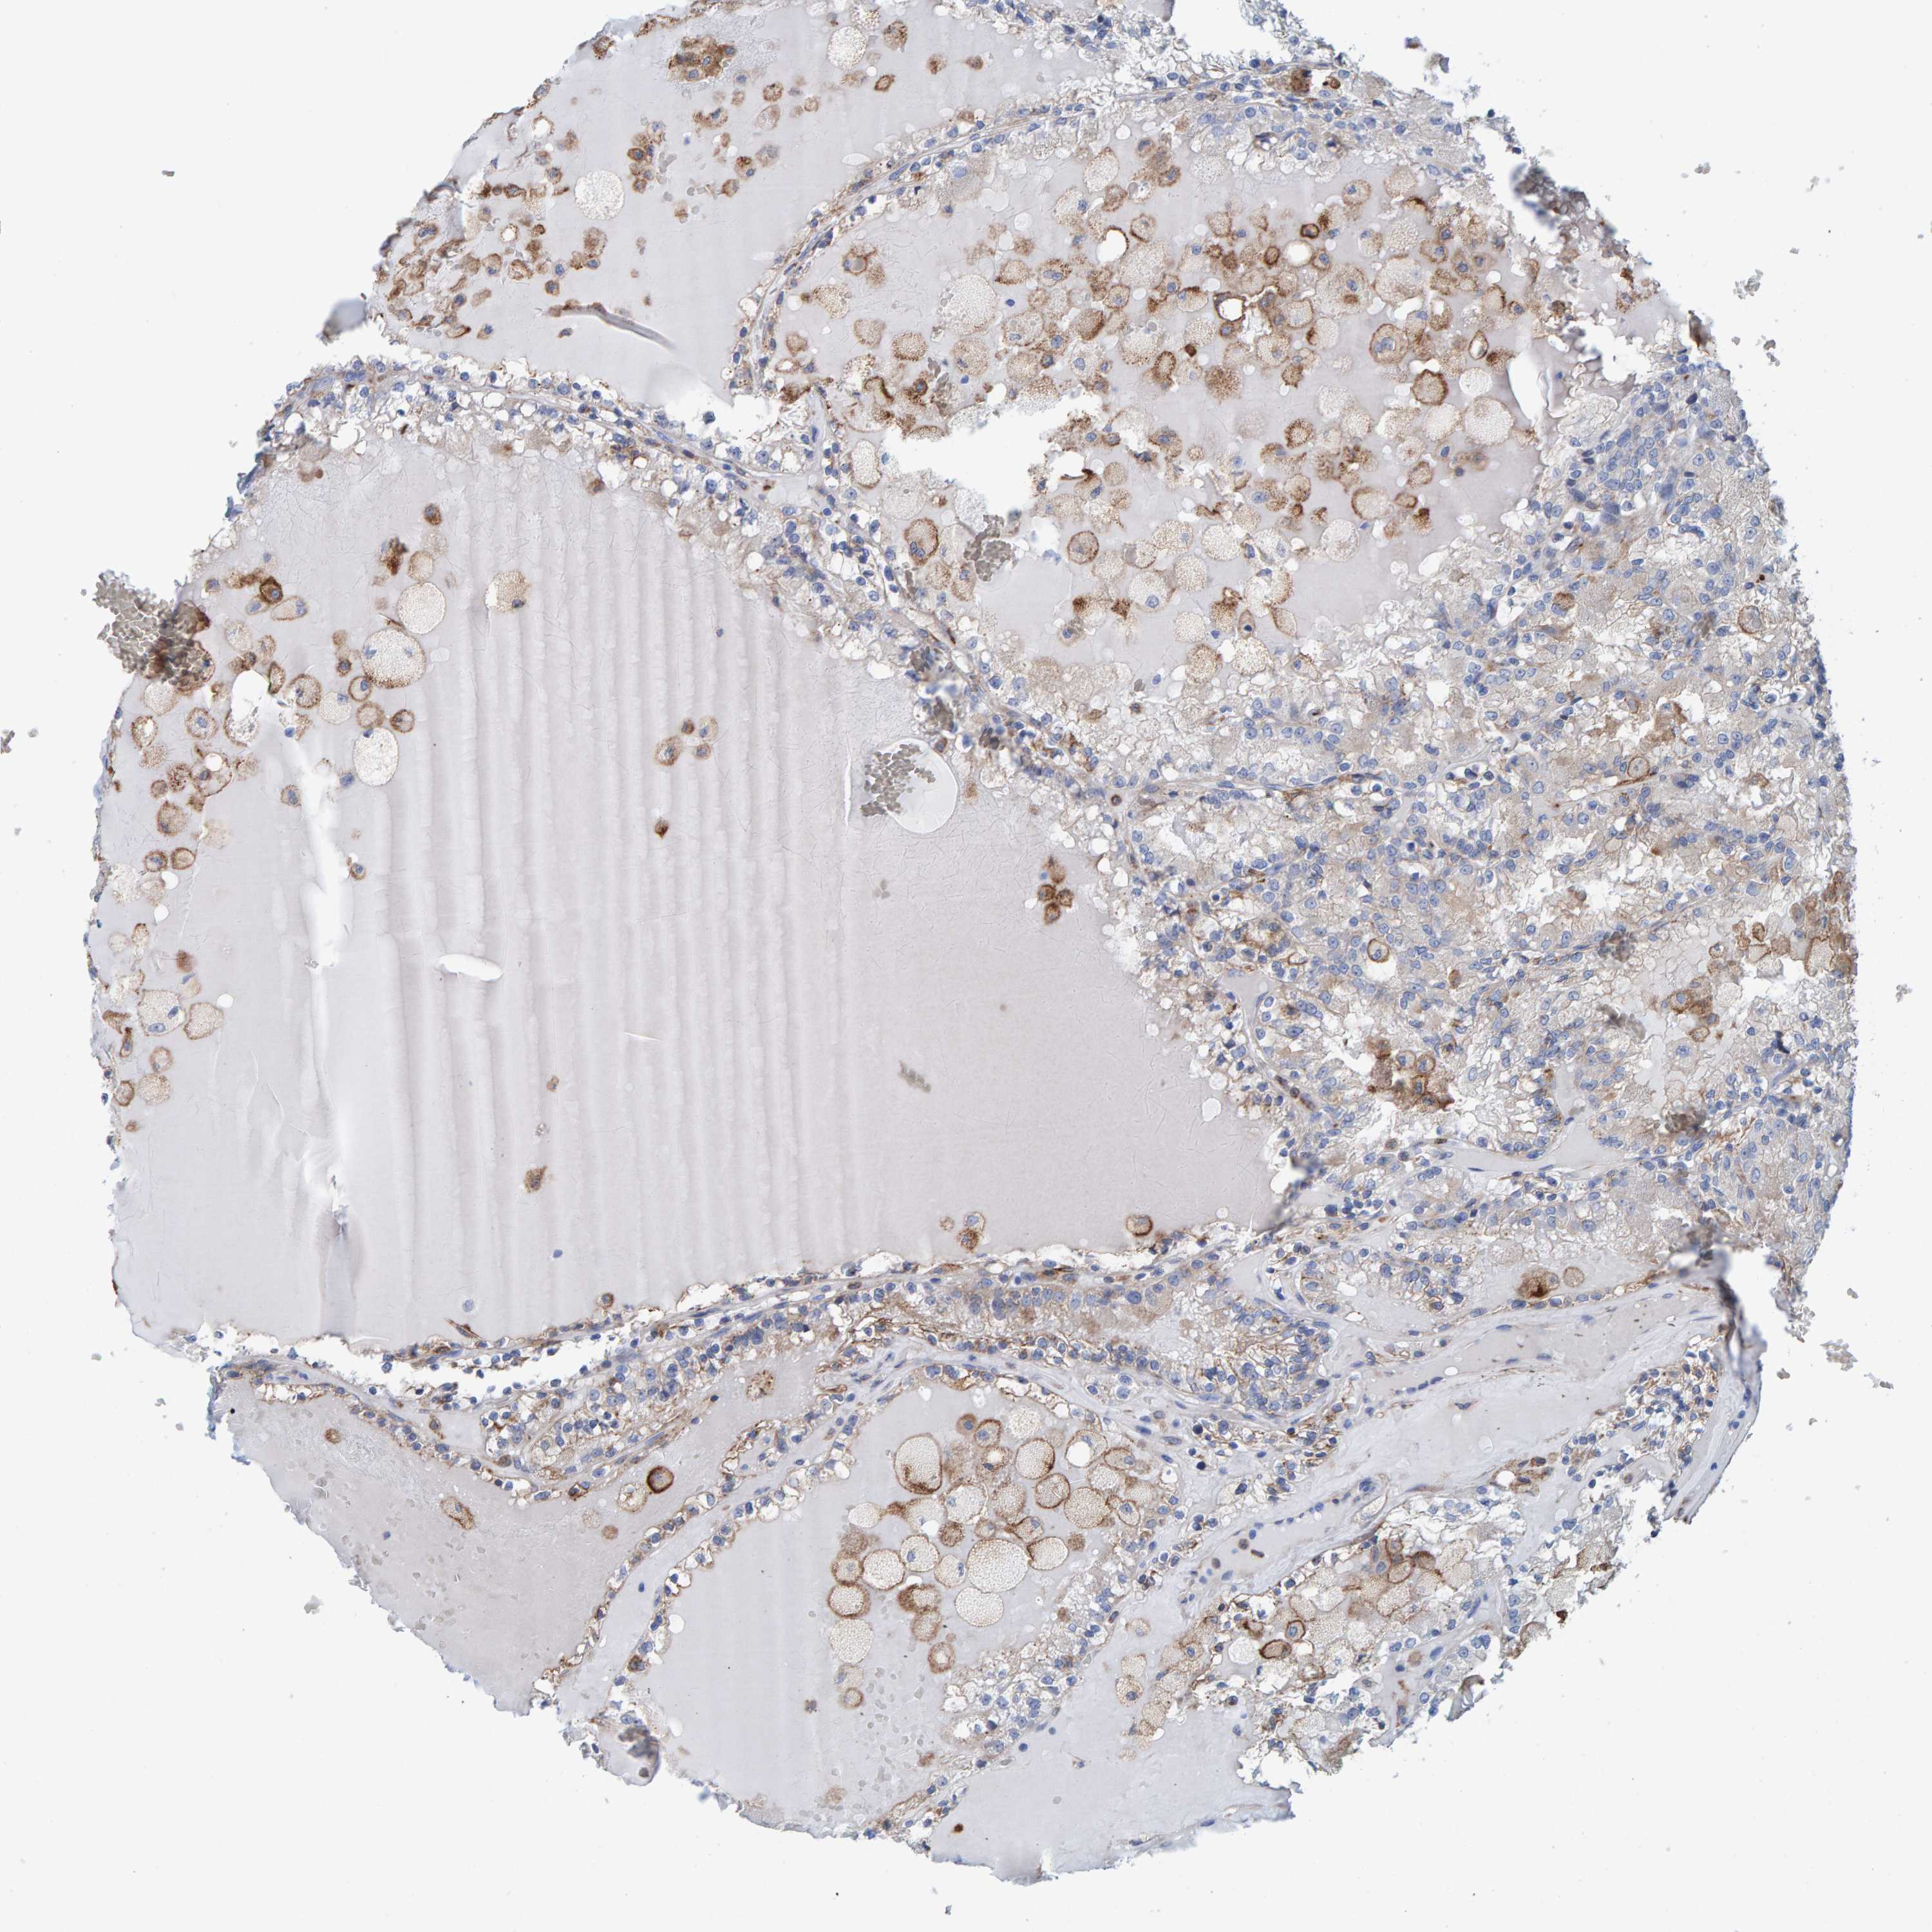

Renal cancer

Kidney renal clear cell carcinoma

KIDNEY RENAL CLEAR CELL CARCINOMA (TCGA) - Interactive survival scatter ploti

LRP1 is potential prognostic, high expression is favorable in Kidney Renal Clear Cell Carcinoma (TCGA)

: 14.9

Average pTPM 30.7

Number of samples 521